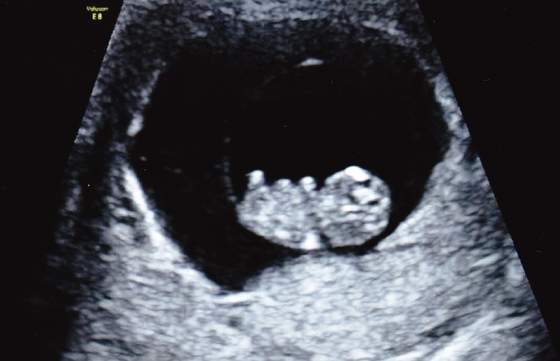

Widziałam malucha, oczywiscie serca bijącego znowu nie zobaczylam od razu

Usg swietne, nie zaluje ani grosza. Byłam z mezem i mala. Super warunki, ja sobie leze, oni wygodnie siedza obok a przed nami wielki tv z fasolka. Posprawdzala babeczka jajniki, macice i wsio co mozna, zadnych problemow, zadnych krwawien czy innych wyciekow w srodku, na jajnikach nie ma torbieli. Serce pieknie bije, pokazala mi przeplyw na sercu i pepowinie, wszystko idealne. Od wtorku fasol wiekszy i dzis juz mial 25,1mm. Termin potwierdzony na 05.08.

Mam zdjecia, wkleje zaraz. w tym jedno z wtorku.